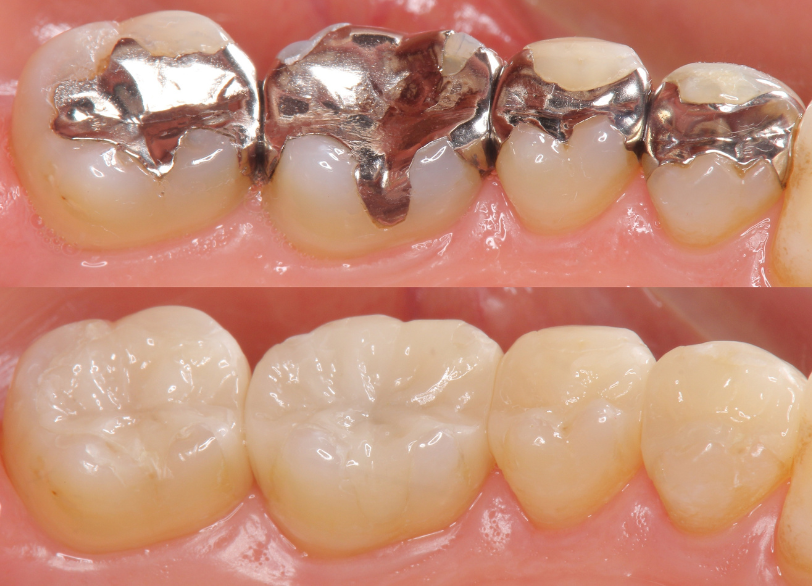

当院の審美治療の大きな柱の一つが、金属を一切使用しない「メタルフリー治療」です。

過去に治療した銀歯(保険診療で一般的に用いられる金銀パラジウム合金)や、アマルガム(水銀を含む古い詰め物)がお口の中に入ってはいないでしょうか。

当院ではメタルフリーの材料を中心に、患者様のご希望や歯の状態に応じて、様々な種類の詰め物・被せ物をご用意しております。

セラミック治療(メタルフリー)

セラミックインレー

|

比較的小さな虫歯を修復するセラミック製の詰め物。 保険の銀歯と異なり白く自然な見た目で、材質の劣化や変色が少ない。 歯と精密に接着するため、二次的な虫歯のリスクも低い。 |

奥歯の小さな虫歯 |